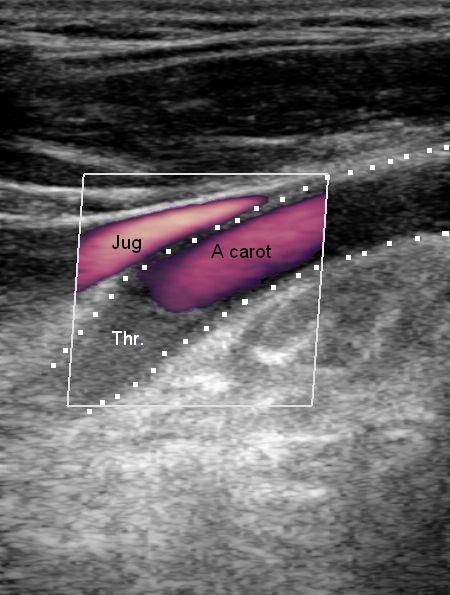

Voila ce que donne une dissection de la carotide interne (A carot.), qui a malheureusement conduit à une thrombose totale (Thr.):

Donc rien de bien spécifique, hormis, quand même la notion classique que ces dissections touchent principalement des zones assez distales de la carotide interne.